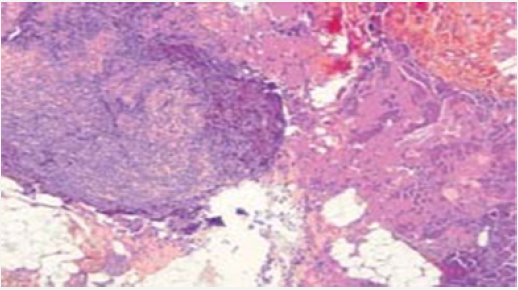

Magnetic resonance imaging (MRI) revealed the presence of intra-orbital processes, retro septal intra and extra-conical, responsible for an exophthalmitis grade 1 right and grade 2 left (Figure 1). A biopsy was made at the block, under general anesthesia and endoscopically, the histopathological examination of the biopsy showed a diffuse proliferation of lymphomatosis cells of medium size, presenting a mature chromatin nucleus and cleaved contour. Immunohistochemistry confirmed the diagnosis of diffuse B-cell lymphoma with negativity of ck and chromogranin and CD3 and CD20 (Figure 2). To date, the patient has received three courses of a polychemotherapy type rituximab-CHOP (ciclophosphamideadriablastinevincristine- prednisolone). The follow-up is only five months but the evolution has been towards a stabilization of the attack.

Figure 2: Infiltration of the orbital muscle and adipose tissue by lymphomatous tumor proliferation.